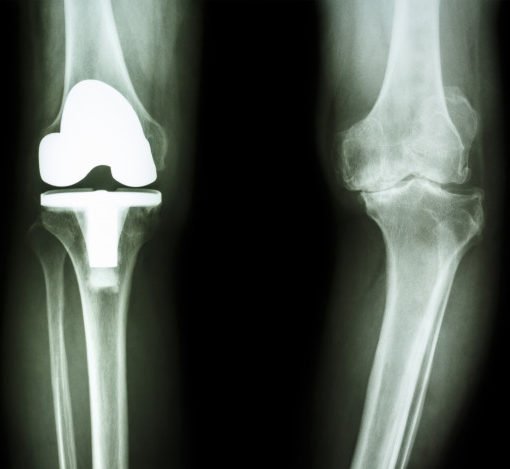

Esempio di Gonartrosi

Esempio di Trattamento con Protesi di Ginocchio

Nel caso in cui la gonartrosi abbia colpito solo un comparto del ginocchio, si ricorre all’intervento per l’impianto della Protesi Monocompartimentale. Questo tipo di intervento si differenzia dalle operazioni tradizionali per la minore invasività a carico dell’articolazione e i tempi di recupero ridotti. Oggi, a differenza del passato, la protesi monocompartimentale del ginocchio è vista come una procedura sicura, affidabile e in grado di garantire un successo a lungo termine.

Se il ginocchio è gravemente danneggiato dall’artrosi in tutti i suoi comparti e i trattamenti non chirurgici per la gonartrosi non sono più efficaci, bisogna prendere in considerazione la protesi totale del ginocchio. L’intervento di protesi totale del ginocchio è sicuro, elimina il dolore e corregge anche eventuali deformità della gamba.